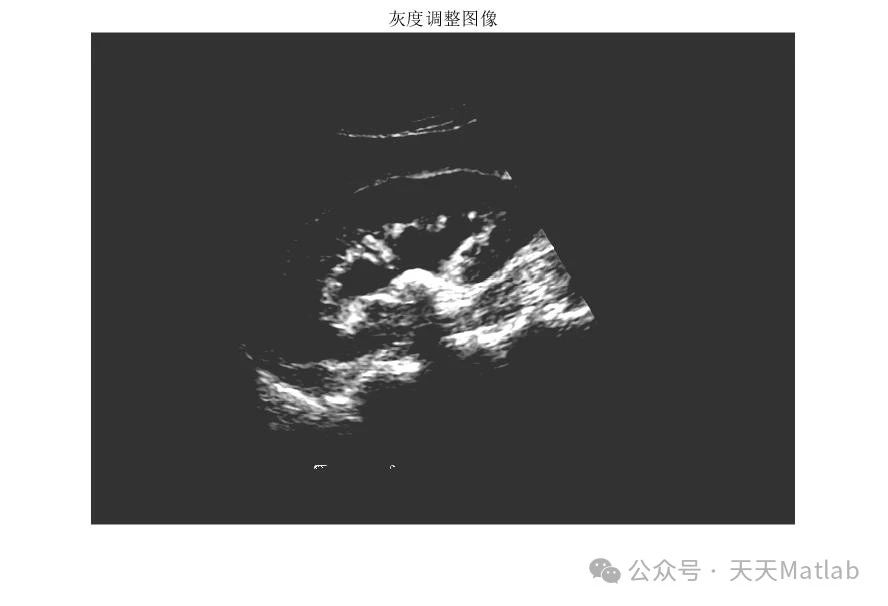

⛳️ 运行结果